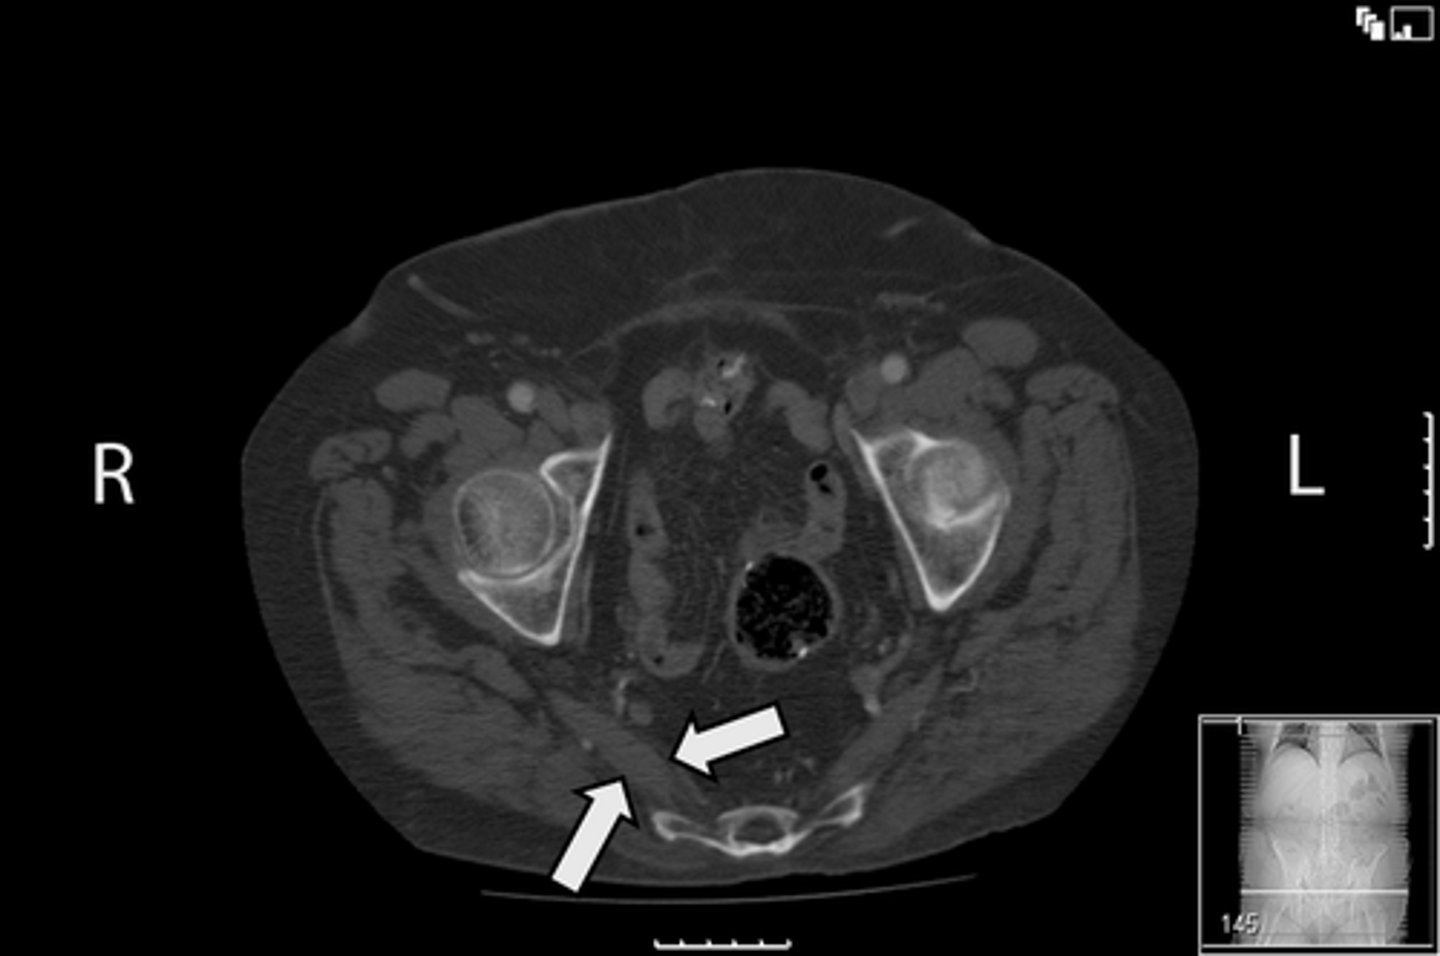

Axial bony pelvis CT

What is the image?

32

L ilium

What is indicated in the image?

<p>What is indicated in the image?</p>

33

New cards

L sacroiliac joint

34

R ilium

35

R sacroiliac joint

36

Sacrum